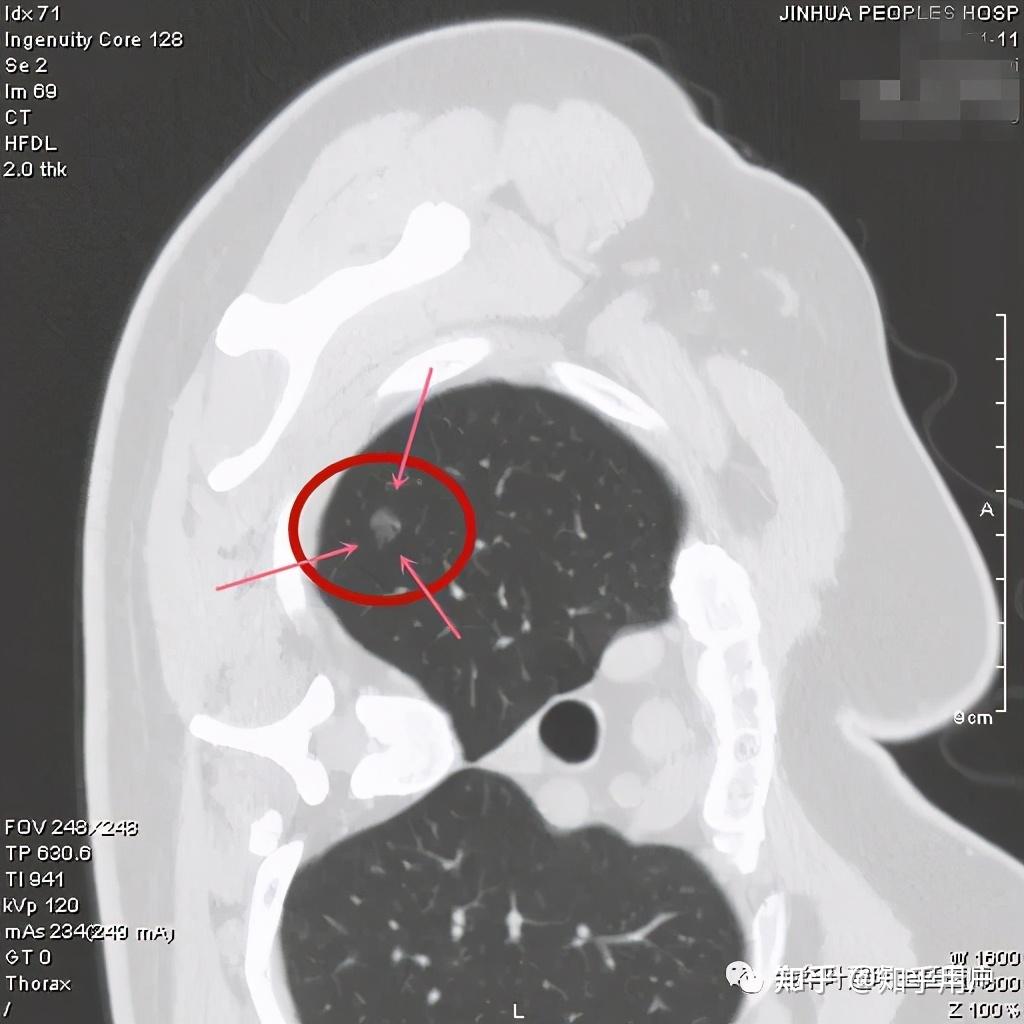

影像上的表现,原位腺癌应该是5-30毫米的纯磨玻璃结节,密度均匀,CT值在-600以下,极少有空泡、毛刺、胸膜牵拉和分叶,可以有血管穿行,但无血管弯曲。当然若病灶在10毫米以上时,诊断原位腺癌要慎重,因为1厘米以上的病理上是原位腺癌的少见。

看着,非常不错,以后原位腺癌与非典型增生不是癌了,不需要手术了,至少不能按恶性肿瘤的方式进行手术了。这是好事!但真的到了临床上,如何把握,我看仍是前路漫漫,迷雾重重!我们先举几个例子,来看看影像上如何来区分AAH、AIS、MIA以及浸润性腺癌。下面的四幅CT图分别各是其中的一种,是我们术后有病理依据确诊的病例,你能分出哪张是哪种吗?

有没有高手能分辨出来?我是一头雾水,根本分不清到底哪个是哪种。都是纯磨玻璃结节,都是瘤肺边界清楚,大小都在1厘米左右或以下。现比如下面这四幅CT图也是分别为AAH、AIS、MIA以及浸润性腺癌(贴壁型),你能分得清楚哪幅图是哪种吗?

这几乎就是四胞胎,长的没什么区别,但病理类型天差地别。现在把AAH与AIS剔除出恶性肿瘤后,更是差别巨大了,是癌与非癌的区别了,但没有手术切除病检的情况下,你如何来区分?